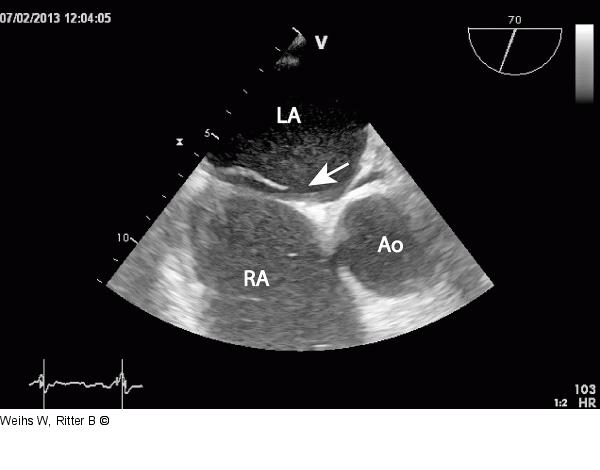

Abbildung 3: Fossa ovalis Einstellung der Fossa ovalis mit einem offenen Foramen ovale (Pfeil). LA: linker Vorhof; RA: rechter Vorhof; Ao: Aorta |

Einstellung der Fossa ovalis mit einem offenen Foramen ovale (Pfeil). LA: linker Vorhof; RA: rechter Vorhof; Ao: Aorta |